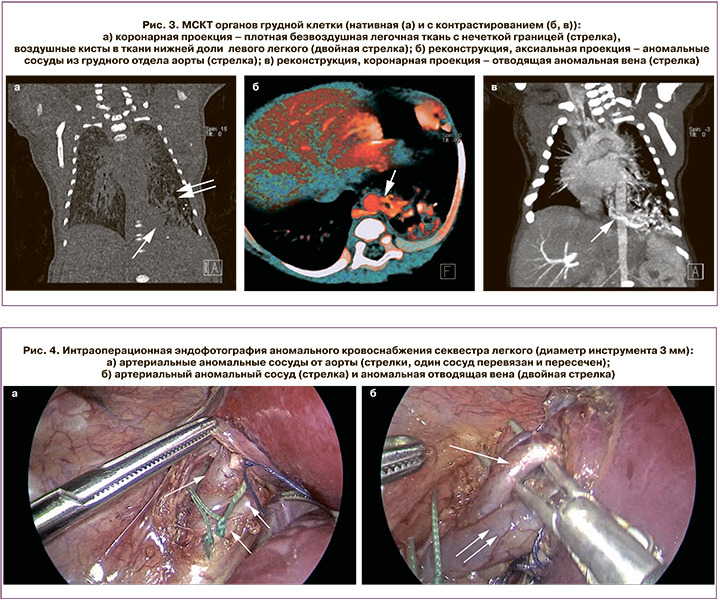

На 6-е сутки жизни выполнена мультиспиральная компьютерная томография (МСКТ) органов грудной клетки с контрастированием: в нижней доле левого легкого расположена зона измененной ткани, представленная мягкотканным компонентом в IX и X сегментах, с неровными нечеткими контурами, по периферии которого, с распространением на VII и VIII сегменты, имеются участки повышенной пневматизации с множественными мелкими воздушными кистами. При контрастировании определяются два аномальных питающих сосуда из нижнегрудного отдела аорты; дренирование крови осуществляется частично по аномальной вене в верхнюю полую вену и правое предсердие, частично по легочным венам в левое предсердие. Остальные отделы правого и левого легких структурно не изменены. Данные изменения соответствуют комбинации интралобарного секвестра и врожденной кистозно-аденоматозной мальформации нижней доли левого легкого (рис. 3).

По достижении стабилизации состояния ребенка на 12-е сутки жизни выполнено оперативное лечение мини-инвазивным торакоскопическим доступом в объеме нижней лобэктомии слева с перевязкой аномальных сосудов (рис. 4). При ревизии выявлены четыре крупных питающих сосуда из нижнегрудного отдела аорты диаметрами 2 мм, два по 4 мм и 3,5 мм, а также отводящая вена в системный кровоток диаметром 5 мм. Лобэктомия выполнена в связи с поражением около 2/3 объема нижней доли левого легкого комбинированным пороком развития. Течение анестезии гладкое. Течение послеоперационного периода гладкое.